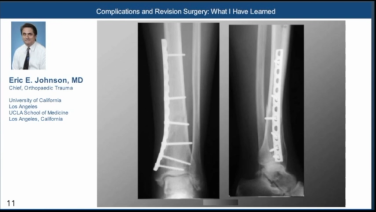

Complications & Revision Surgery with Eric Johnson, MD